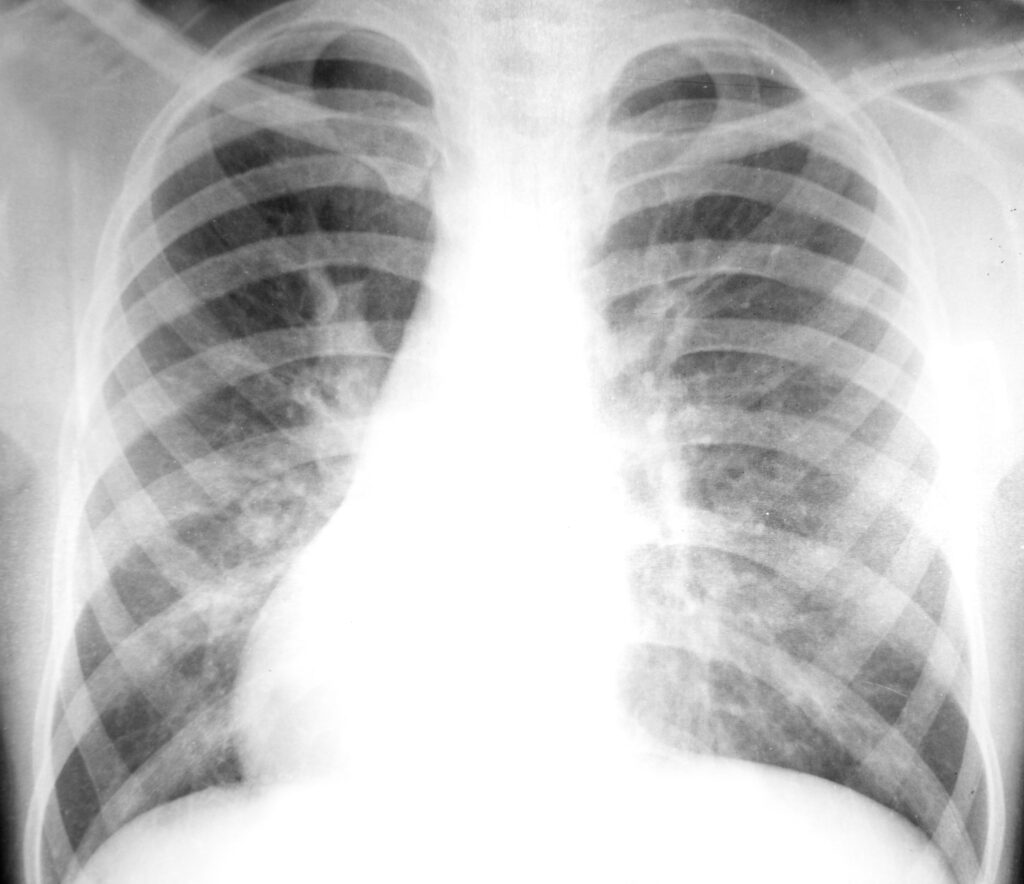

Pleural Mesothelioma

Pleural Mesothelioma Mesothelioma is cancer in the membrane of various organs. Pleural mesothelioma, also called malignant pleural mesothelioma or MPM, is found in the membrane between the lungs and chest wall, called the pleura. Without treatment, the average life expectancy of pleural mesothelioma is six months following diagnosis. Mesothelioma surgery, chemotherapy, radiation therapy, and other […]